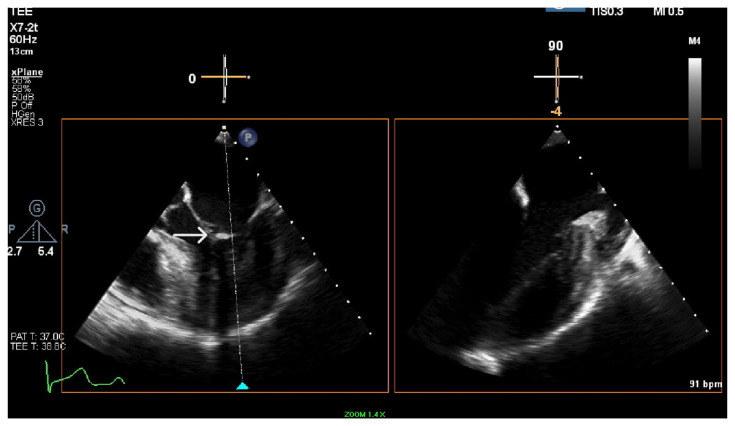

Case description: We present a 58-year-old African American woman with multiple comorbidities, including end-stage renal disease, on hemodialysis who presented with altered mentation. On investigations, she had A. oris bacteremia, with echocardiography revealing mitral valve vegetation. She was treated with IV antibiotics followed by oral amoxicillin-clavulanic acid.

Discussion: Our case highlights the diagnostic challenges posed by slow-growing organisms like A. oris in patients with comorbidities, especially on hemodialysis. Blood cultures and transesophageal echocardiography were critical in diagnosing this case. Advanced microbial diagnostic techniques are crucial in identifying the pathogen and the pathogen's susceptibility-guided treatment. This case highlights the importance of early recognition and tailored therapy for rare pathogens like A. oris.